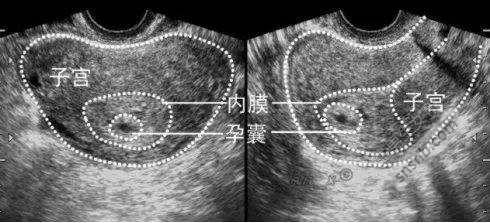

二、孕囊形状

有人认为从孕囊形状可以看出肚子里的宝宝是男是女,这是有一定道理的。通常情况下,如果孕囊的形状像茄子,或者是呈长条状的,怀的是男宝宝的可能性较大;而如果孕囊是椭圆形或圆形的,则怀女宝宝的可能性较大。